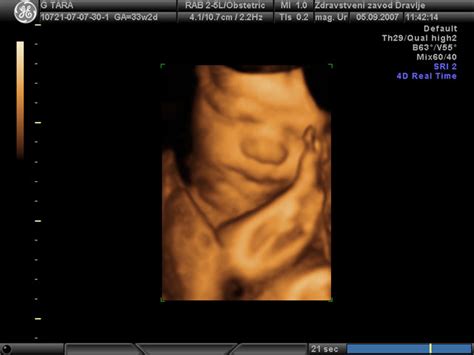

Čeprav je ultrazvok zelo natančen za oceno rasti in anatomije ploda, lahko dejavniki, kot so položaj ploda, teža matere in gestacijska starost, vplivajo na natančnost. 3D in 4D ultrazvok ponujata tridimenzionalne slike in gibanje v realnem času. V posebnih primerih se lahko uporabijo alternative, kot je magnetna resonanca (MRI), za podrobnejše preglede mehkih tkiv.

V zadnji tretjini nosečnosti plod pridobiva na teži in se nadalje razvija. V tem času je priporočljivo opraviti kontrolo plodovega stanja, rasti in kondicije, običajno med 30. in 32. tednom nosečnosti. Z meritvijo obsega in premera glave, obsega trebuha in dolžine stegnenice se določi telesna teža ploda, kar pomaga prepoznati morebitno zaostajanje v razvoju. V takšnih primerih se natančneje oceni stanje ploda z meritvijo pretokov krvi skozi popkovnico. V primeru medenične vstave ali prečne lege ploda je priporočljiva kontrola lege v 36. tednu. Po 36. tednu se nadaljnje kontrole prilagodijo glede na posamezen primer.